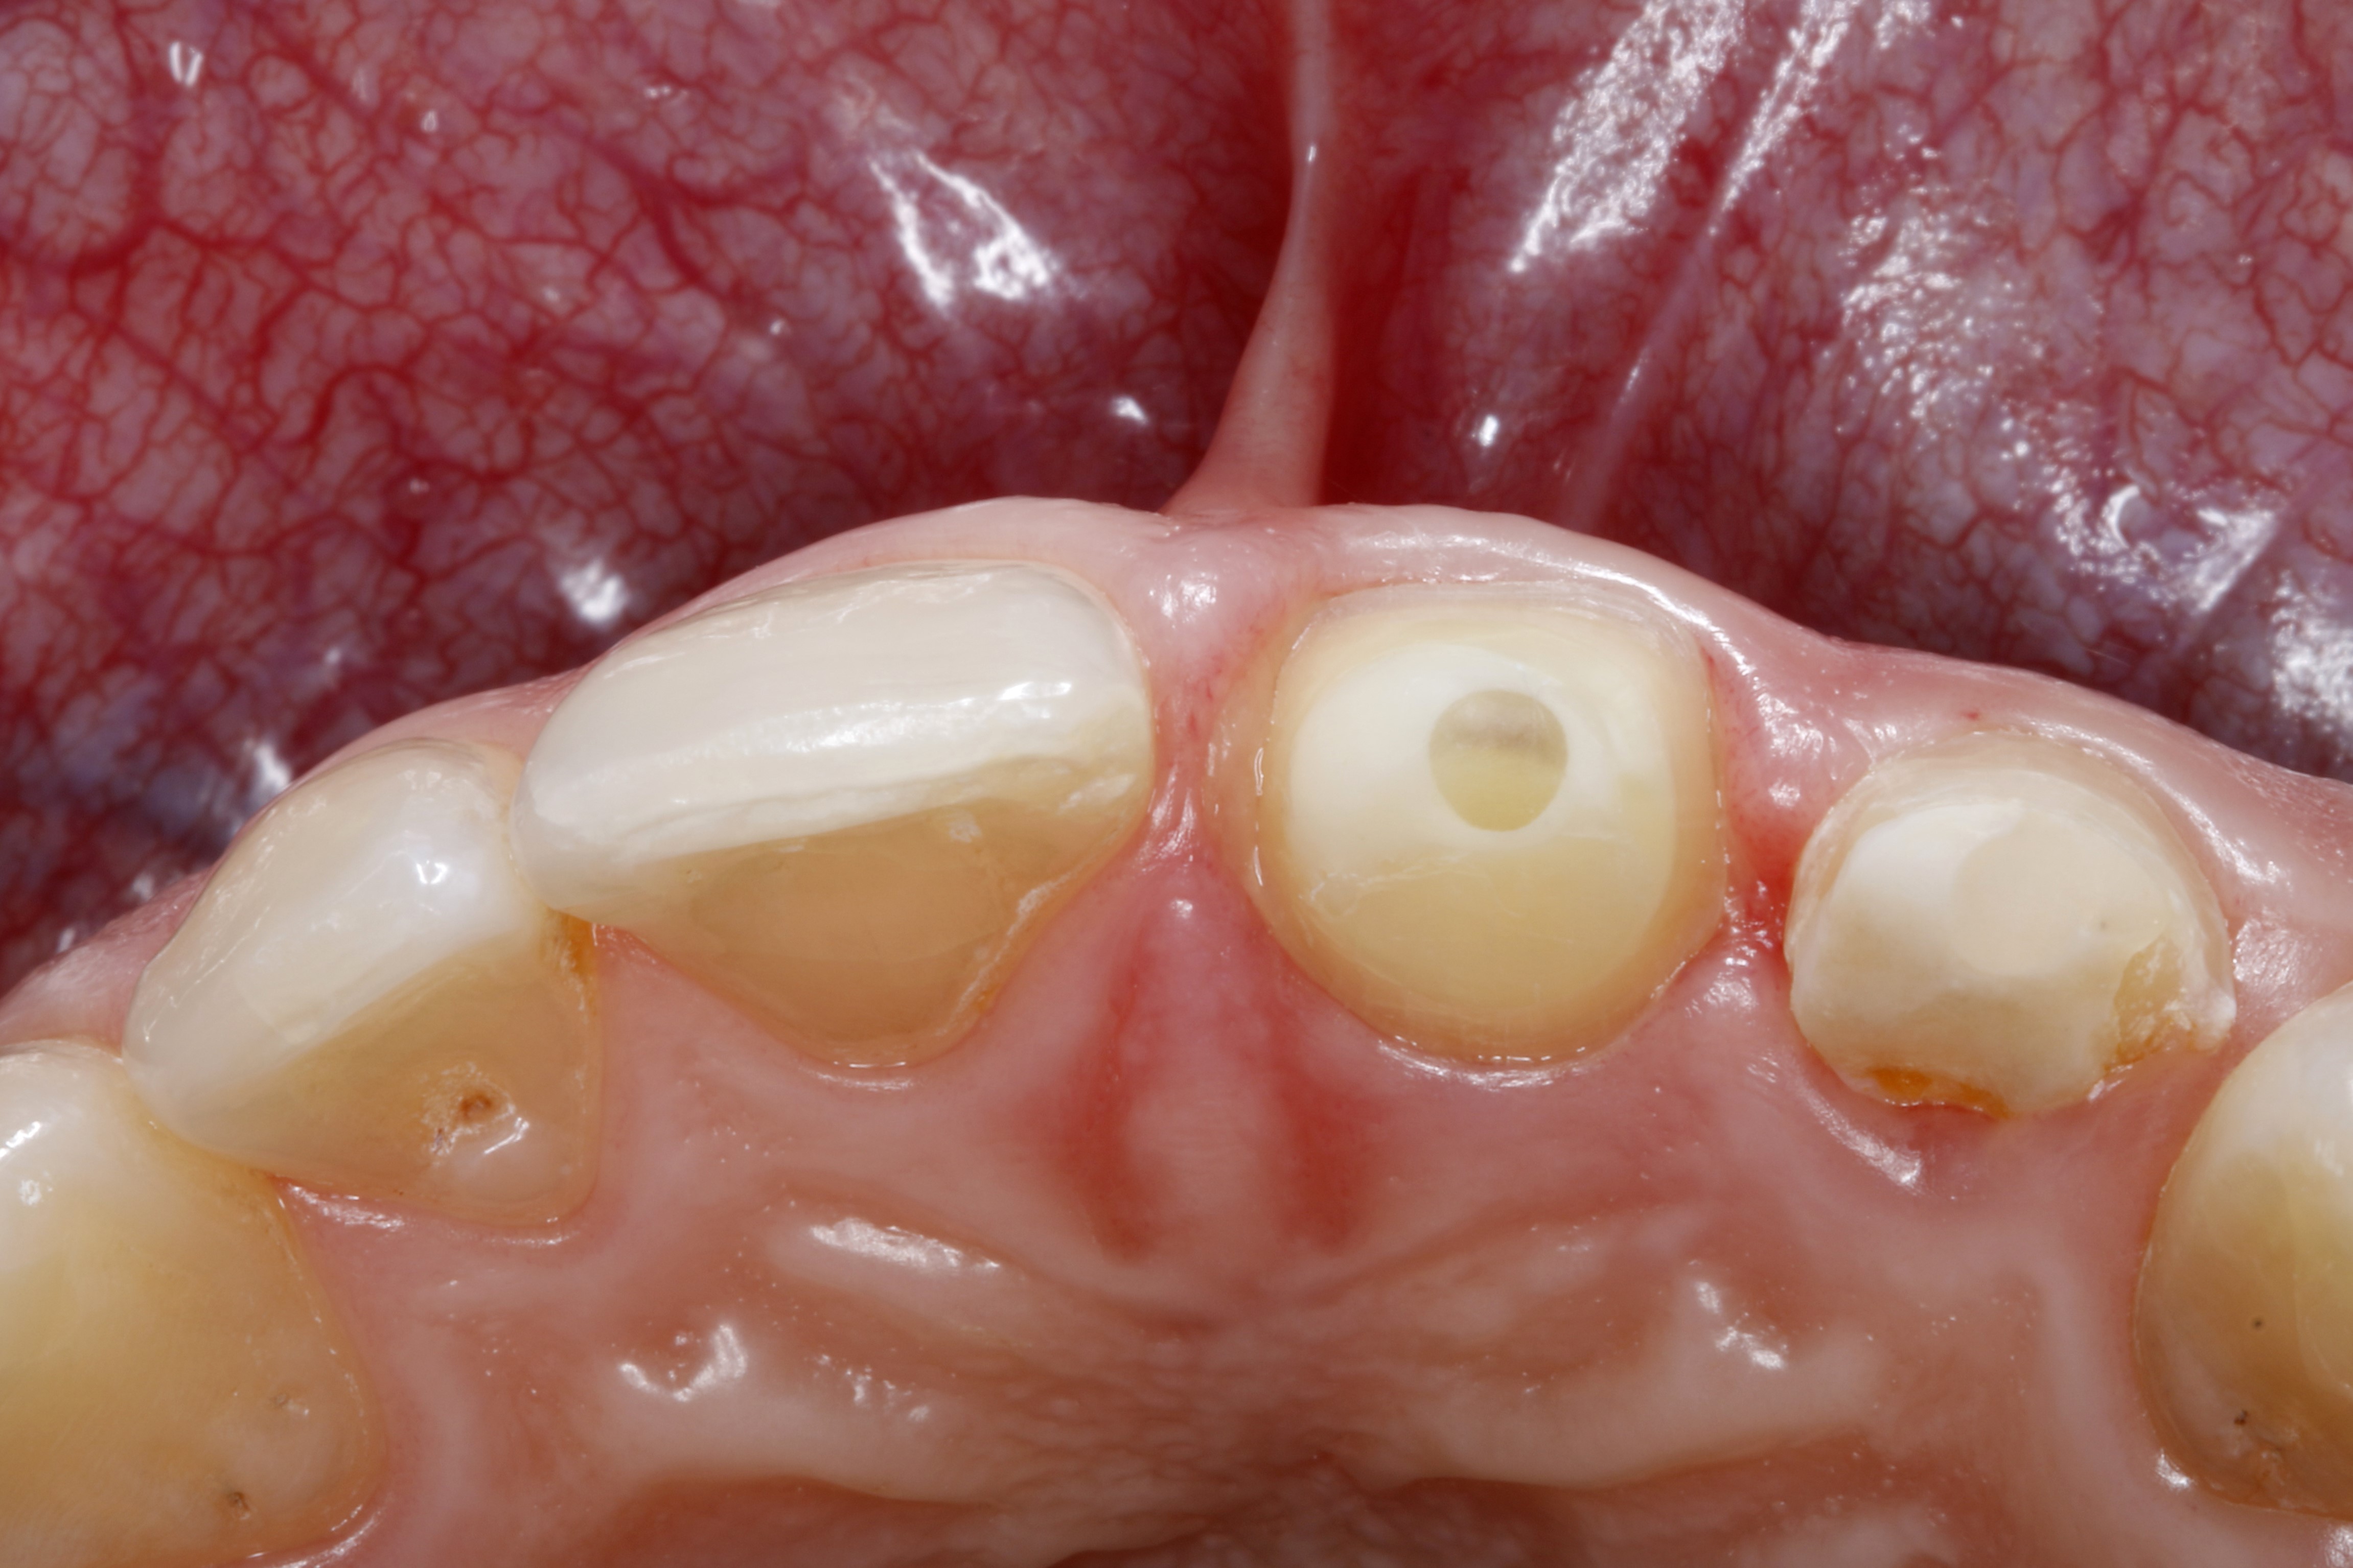

Ryc. 4. Ząb 21 od strony brzegu siecznego – widoczny zacementowany adhezyjnie, wzmocniony włóknem szklanym wkład koronowo‑korzeniowy (Rebilda Post, VOCO).